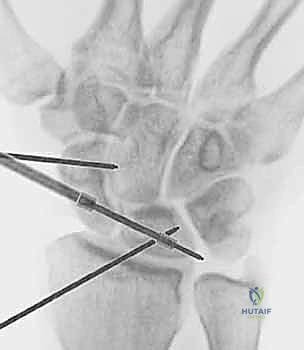

- Technique (Scapholunate Pinning):

- Reduction: First, we must achieve an anatomical reduction of the scapholunate interval. This is often accomplished by direct manual pressure on the scaphoid tubercle and lunate, or by using a small probe to manipulate the bones into alignment. We'll confirm reduction with fluoroscopy.

- Pin Placement: We typically use two 0.045-inch Kirschner wires. The first K-wire is usually inserted from the scaphoid, across the scapholunate joint, into the lunate. The entry point on the scaphoid is typically on its dorsal-radial aspect.

- Fluoroscopic Guidance: This step is absolutely critical. We'll use the mini C-arm to guide the K-wire placement. We need to ensure the wire is:

- Intra-articular: Crossing the scapholunate joint without violating the radioscaphoid or capitolunate joint.

- Central in the bones: Avoiding the edges to prevent breakage and maximize purchase.

- Parallel: The two wires should be parallel to each other, approximately 2-3 mm apart.

- Adequate Length: Sufficiently long to engage both the scaphoid and lunate without protruding excessively.

- Second Pin: A second K-wire is placed in a similar fashion for rotational stability.

- Pin Bending and Capping: Once satisfied with the position on fluoroscopy, the K-wires are cut and bent outside the skin, then capped to prevent migration and skin irritation.

FIG 5 • A. Percutaneous pinning of the scapholunate joint using two K-wires.

FIG 5 • B. Fluoroscopic image confirming satisfactory K-wire placement.

- Technique (Lunotriquetral Pinning):

- Reduction: Reduce the lunotriquetral joint, often by applying pressure to the triquetrum and lunate.

- Pin Placement: Two 0.045-inch K-wires are typically inserted from the triquetrum, across the lunotriquetral joint, into the lunate. The entry point on the triquetrum is usually on its dorsal-ulnar aspect.

- Fluoroscopic Guidance: Similar to SLIL pinning, ensure intra-articular, central, parallel, and adequate length placement under fluoroscopic control.